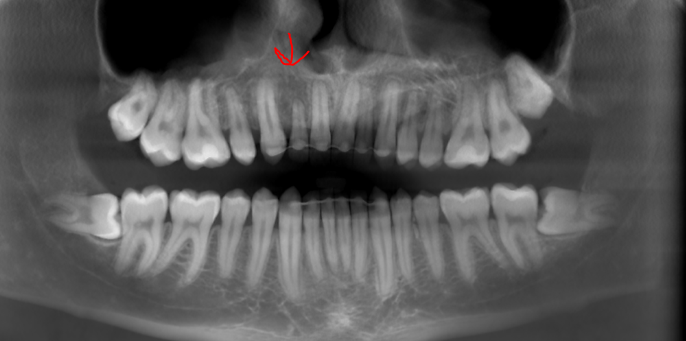

you can also see that my alveolar bone is short af vertically which causes lot of issues like lack of upper teeth show and small root on the teeth. in particularry my right incisor is hanging off by a thread:feelswah:

you cant see the roots there properly, here let me show you: